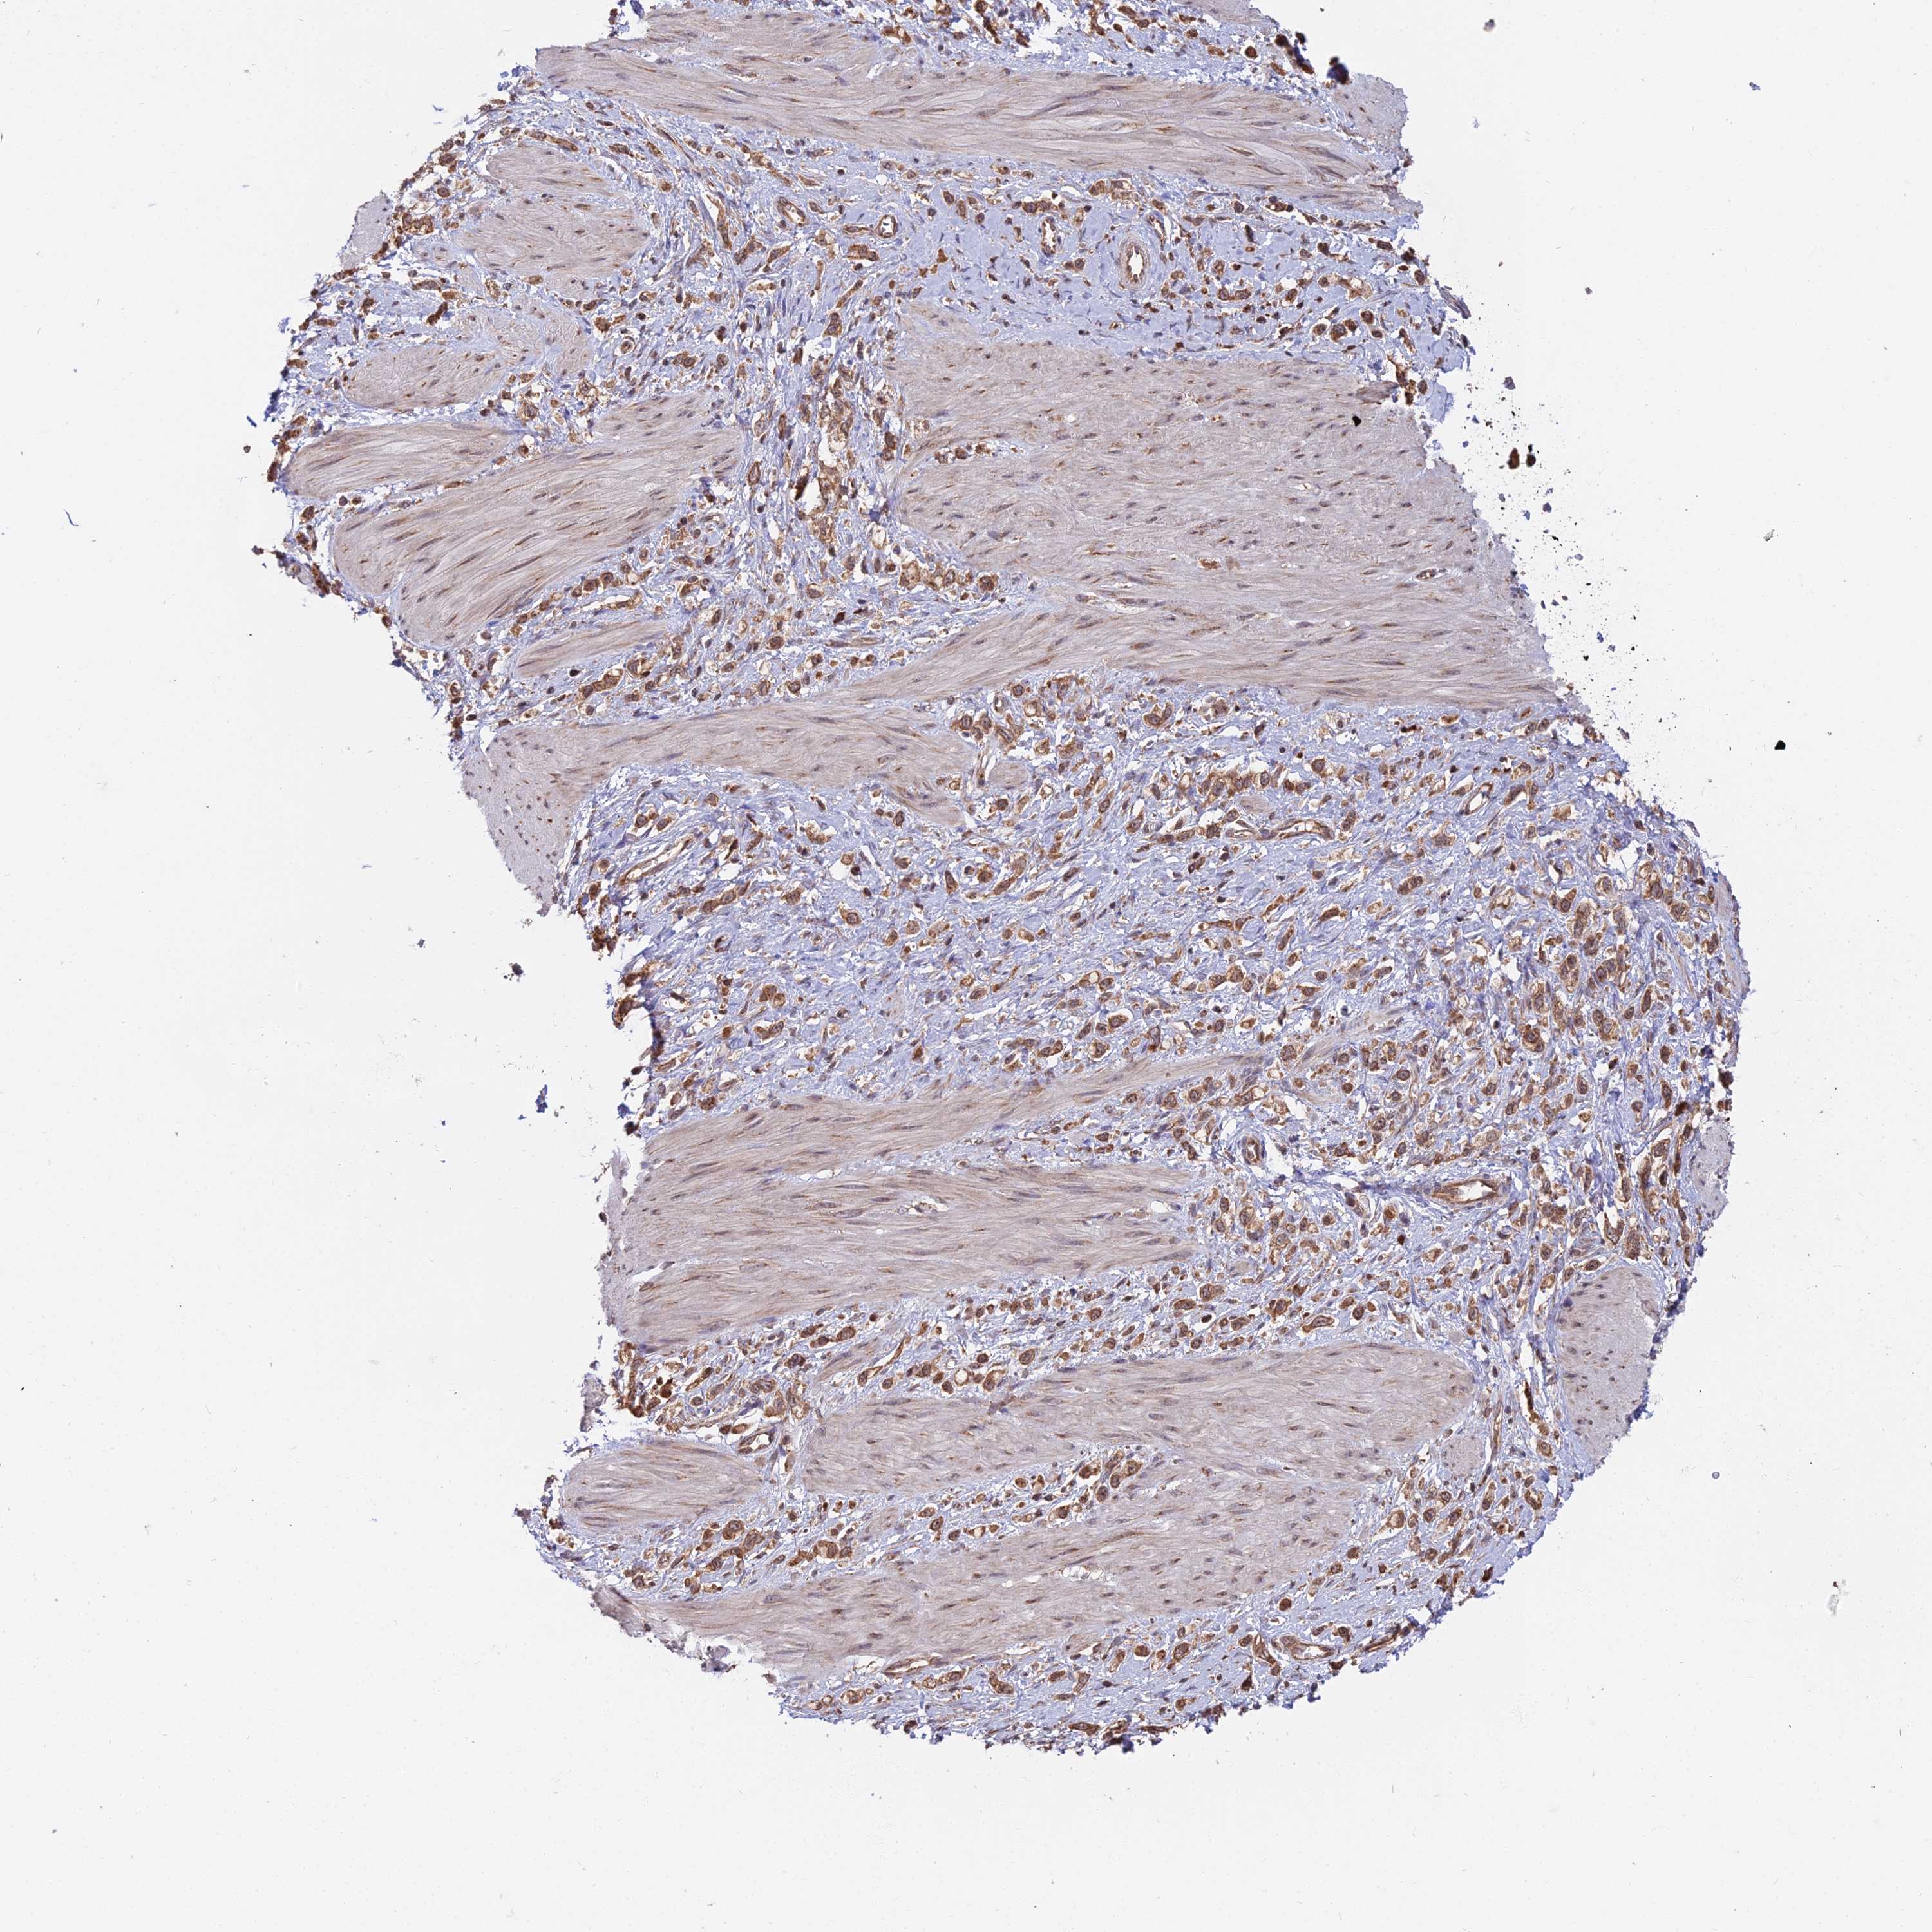

STOMACH CANCER - Protein expressioni

A mouse-over function shows sample information and annotation data. Click on an image to view it in a full screen mode. Samples can be filtered based on level of antibody staining by selecting one or several of the following categories: high, medium, low and not detected. The assay and annotation is described here.

Note that samples used for immunohistochemistry by the Human Protein Atlas do not correspond to samples in the TCGA dataset.

Antibody stainingi

Antibody staining in the annotated cell types in the current human tissue is reported as not detected, low, medium, or high, based on conventional immunohistochemistry profiling in selected tissues. This score is based on the combination of the staining intensity and fraction of stained cells.

Each image is clickable and will lead to virtual microscopy that enables deeper exploration of all samples and also displays staining intensity scores, fraction scores and subcellular localization as well as patient and tissue information for each sample.

Antibody HPA030449

Antibody CAB037301

Staining

High

Medium

Low

Not detected

Intensity

Strong

Moderate

Weak

Negative

Quantity

>75%

75%-25%

<25%

None

Location

Nuclear

Cytoplasmic/membranous

Cytoplasmic/membranous,nuclear

Adenocarcinoma, NOS